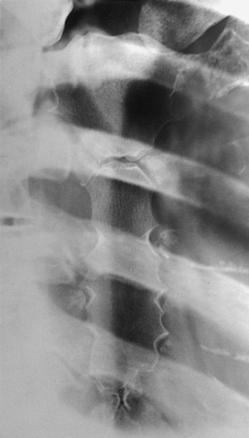

Posteriorly, the head of a rib is closely bound to the demifacets of two adjacent vertebral bodies to form a synovial gliding articulation called the costovertebral joint (Fig. 9-7, A; see Fig. 9-6). The 1st, 10th, 11th, and 12th ribs each articulate with only one vertebral body.

The tubercle of a rib articulates with the anterior surface of the transverse process of the lower vertebra at the costotransverse joint, and the head of the rib articulates at the costovertebral joint. The head of the rib also articulates with the body of the same vertebra and articulates with the vertebra directly above. The costotransverse articulation is also a synovial gliding articulation. The articulations between the tubercles of the ribs and the transverse processes of the vertebrae permit only superior and inferior movements of the first six pairs. Greater freedom of movement is permitted in the succeeding four pairs.